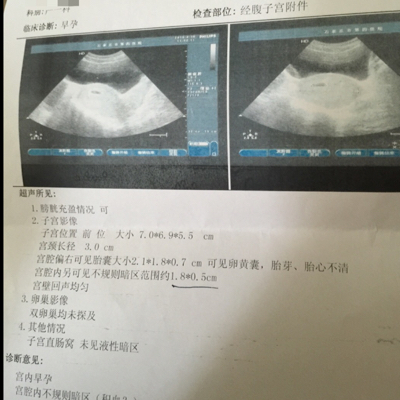

你们看看 我现在5周 6天 这个胎囊大小正常吗 还有宫腔内有不规则阴影 大夫说有先兆流产的迹象 说的我怕呼呼的 育儿问答 宝宝树

怀孕5周 3时有褐色分泌物去医院b超没看到胎囊 过了3天又去医院 这次阴超看见胎囊了位置比较低 孕酮也低6 17来了黄体酮和固肾保胎丸 吃药3天今天又出血了 育儿问答 宝宝树

孕早期胚胎发育好不好 这几大关键指标给你答案

孕早期胚胎发育好不好 这几大关键指标给你答案 网易订阅

孕早期b超能告诉我们什么 知乎